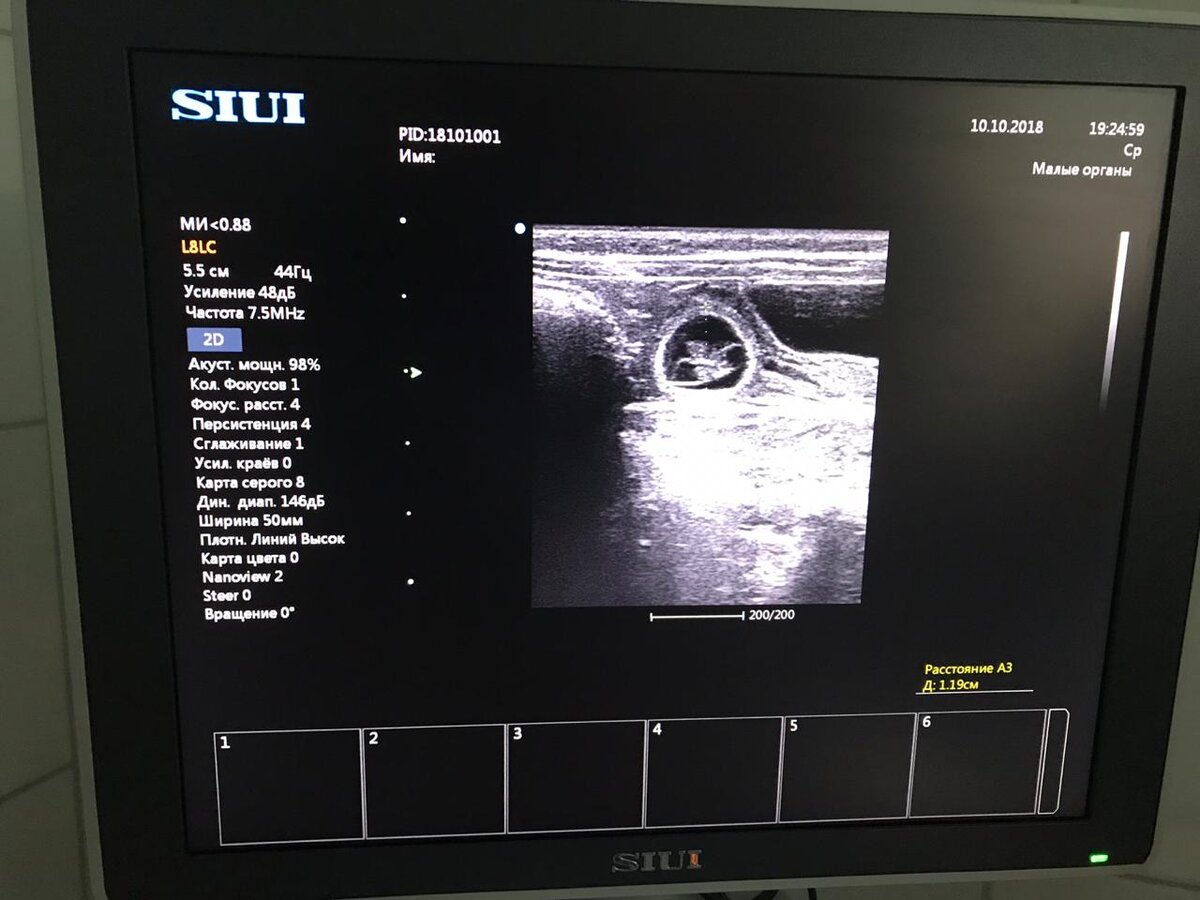

Так выглядит Узи на сроке 10-12 дней

УЗи беременности обычно делают на сроках не раньше 3 недель, но если УЗИ аппарат хороший, экспертного класса - то можно увидеть и раньше. Даже в 2 недели и даже - в 10 дней!!! В ветеринарной клинике "Василек" - именно такой аппарат, и вы все можете с легкостью увидеть на фото выше округлые пузыри с зародышем внутри!